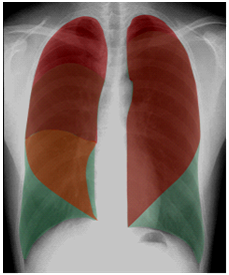

正常胸片